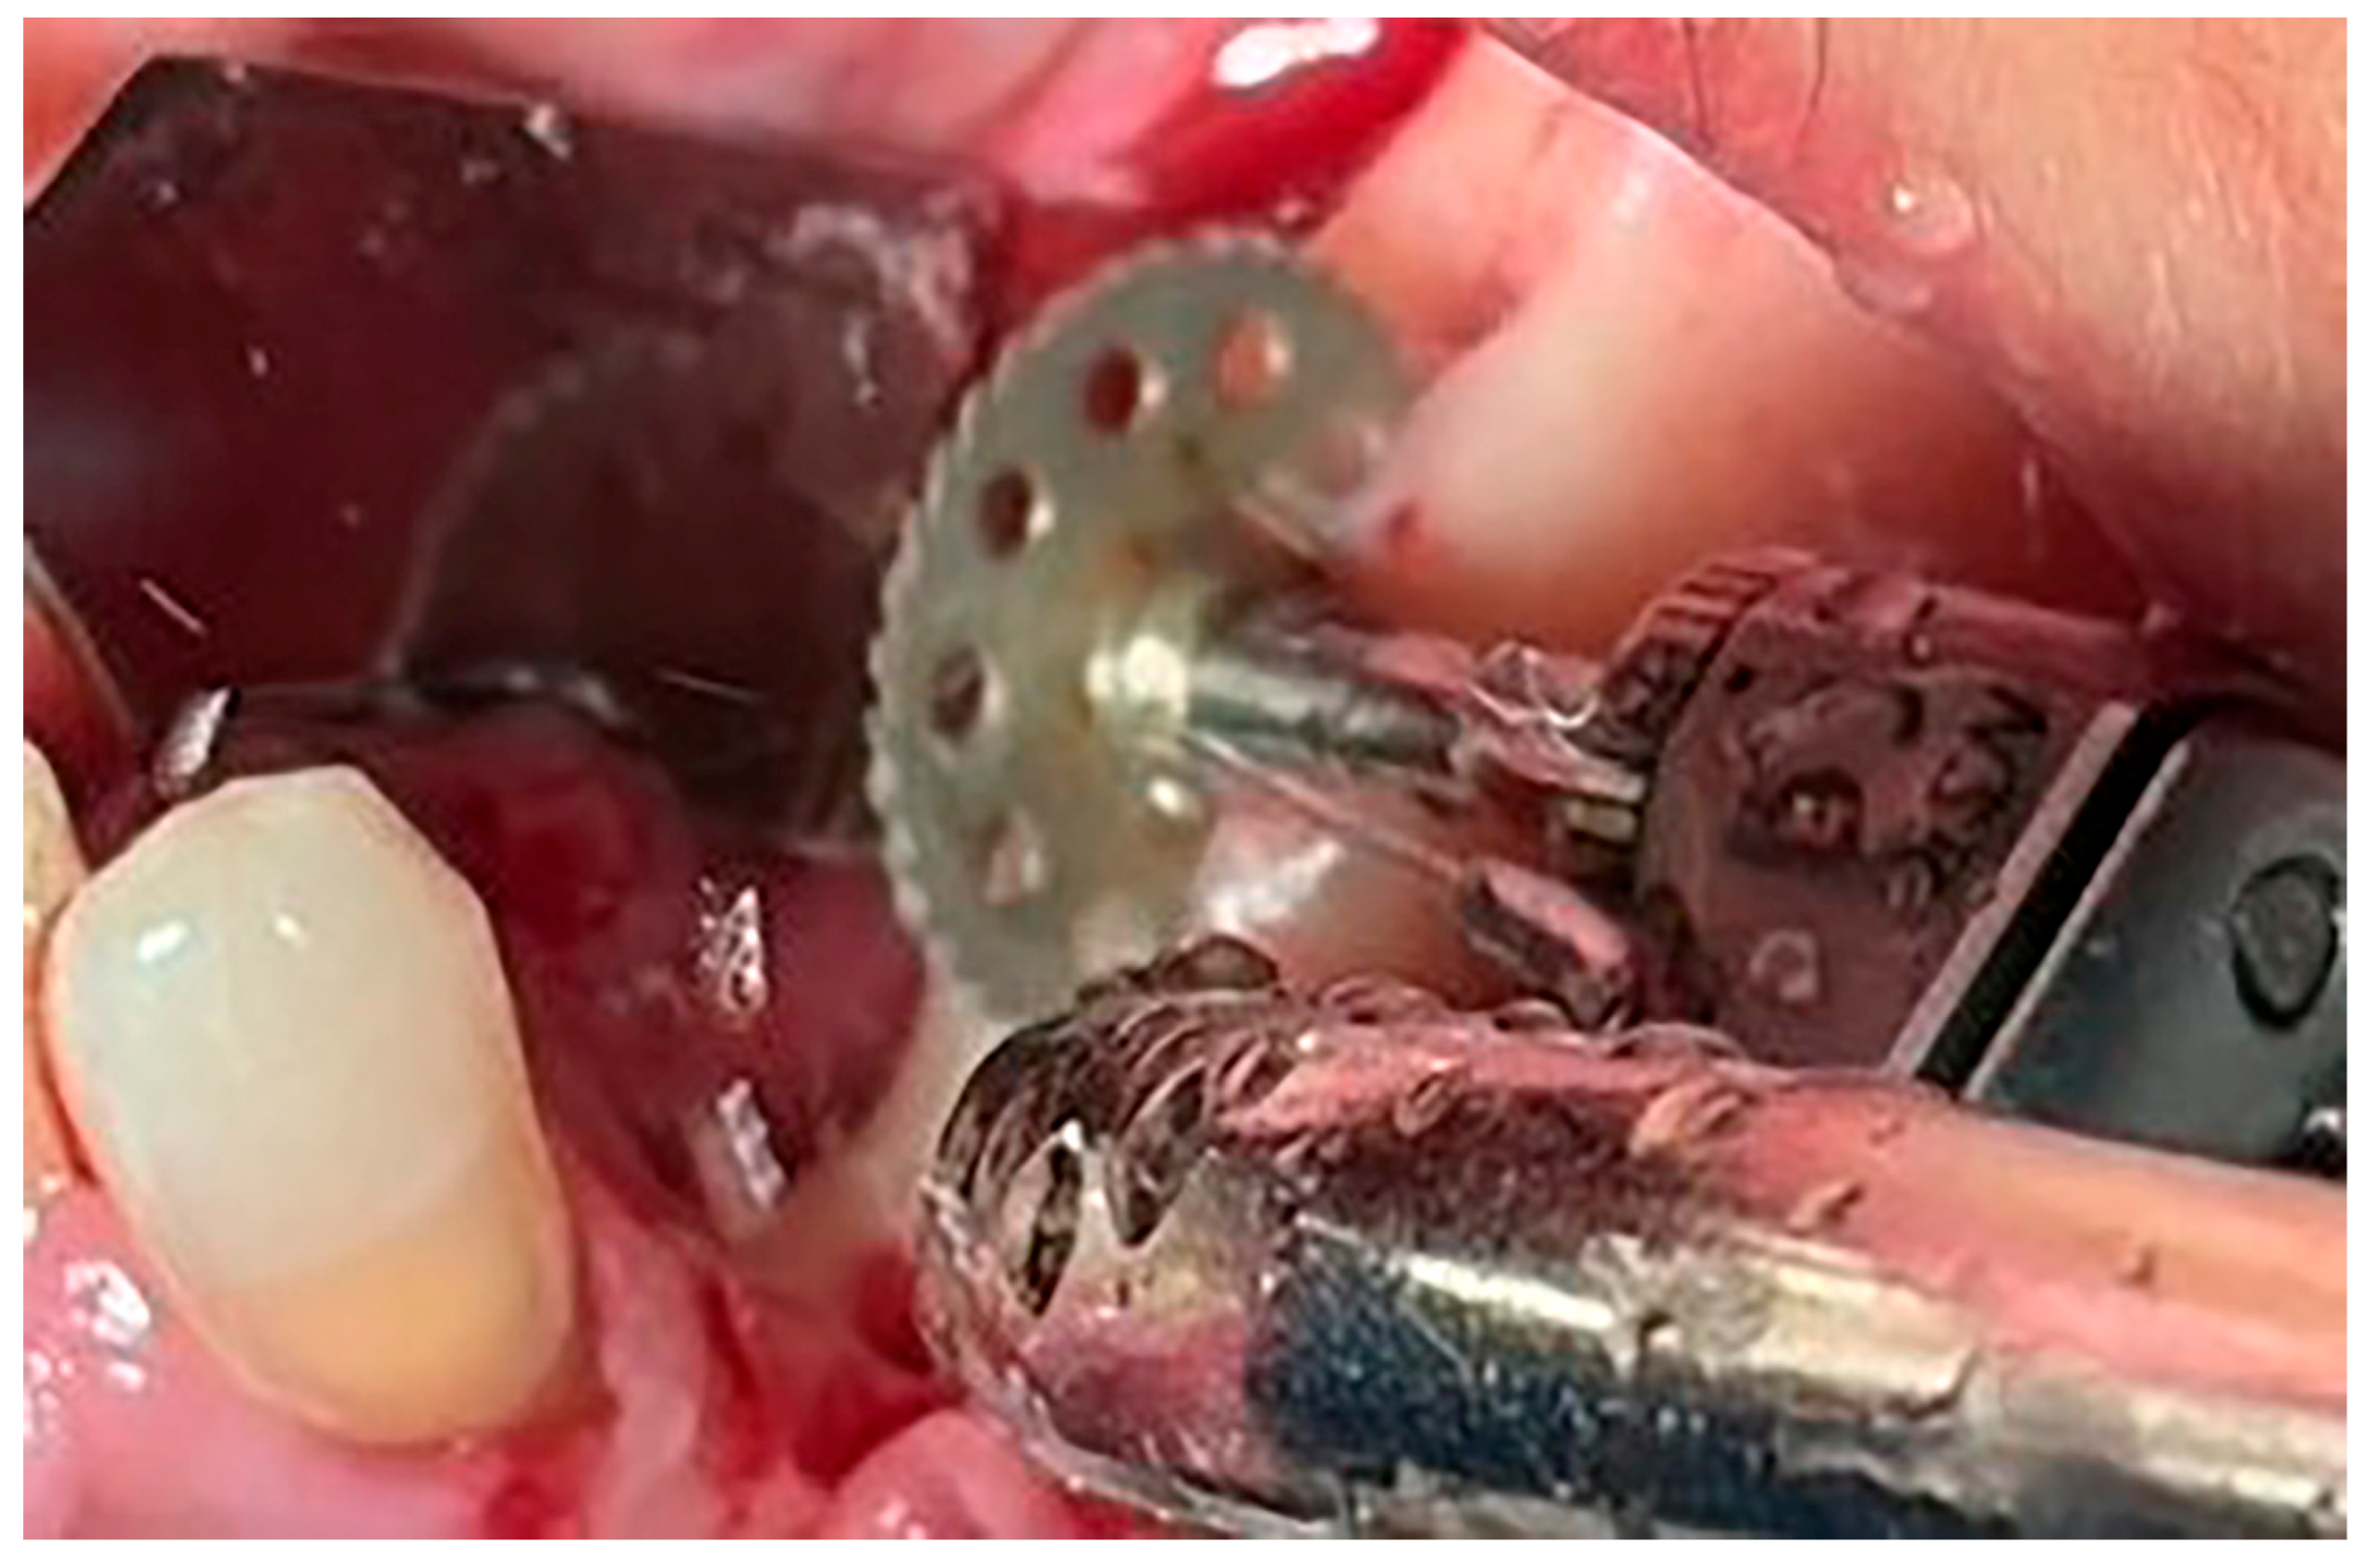

Local anesthesia using 4% articaine with adrenaline 1:100,000 (Septanest®, Septodont, Saint-Maur-des-Fossés, France) was administered. After the midcrestal longitudinal incision, a full thickness mucoperiosteal flap without a vertical releasing incision was elevated and the top of the alveolar ridge was flattened to the width of 4 mm (Figure 3). Preparation of the implant bed was performed with only one twist drill from the set (Esset kit®, Osstem, Seoul, Republic of Korea) which corresponded to the implant length (Figure 4). Following the preparation of the implant bed with the twist drill, a midcrestal longitudinal osteotomy was performed with a special saw with the speed of 1200 rpm (Figure 5). A specially designed set of expanders (Esset kit®, Osstem, Seoul, Republic of Korea) was used gradually in order to separate the buccal plate from the lingual cortical plate, according to their elasticity (Figure 6A–C).

Figure 3. Flattening of the top of the alveolar crest to the level of 4 mm.